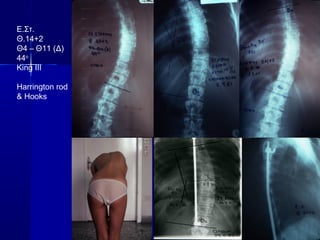

64. Ε. Φρ.Ε. Φρ.

ΘΘ –– 16+1016+10

ΘΘ66 - Θ- Θ1111 (Δ) 70(Δ) 70οο

ΘΘ1212 - Ο- Ο44 (Α) 52(Α) 52οο

King IIKing II